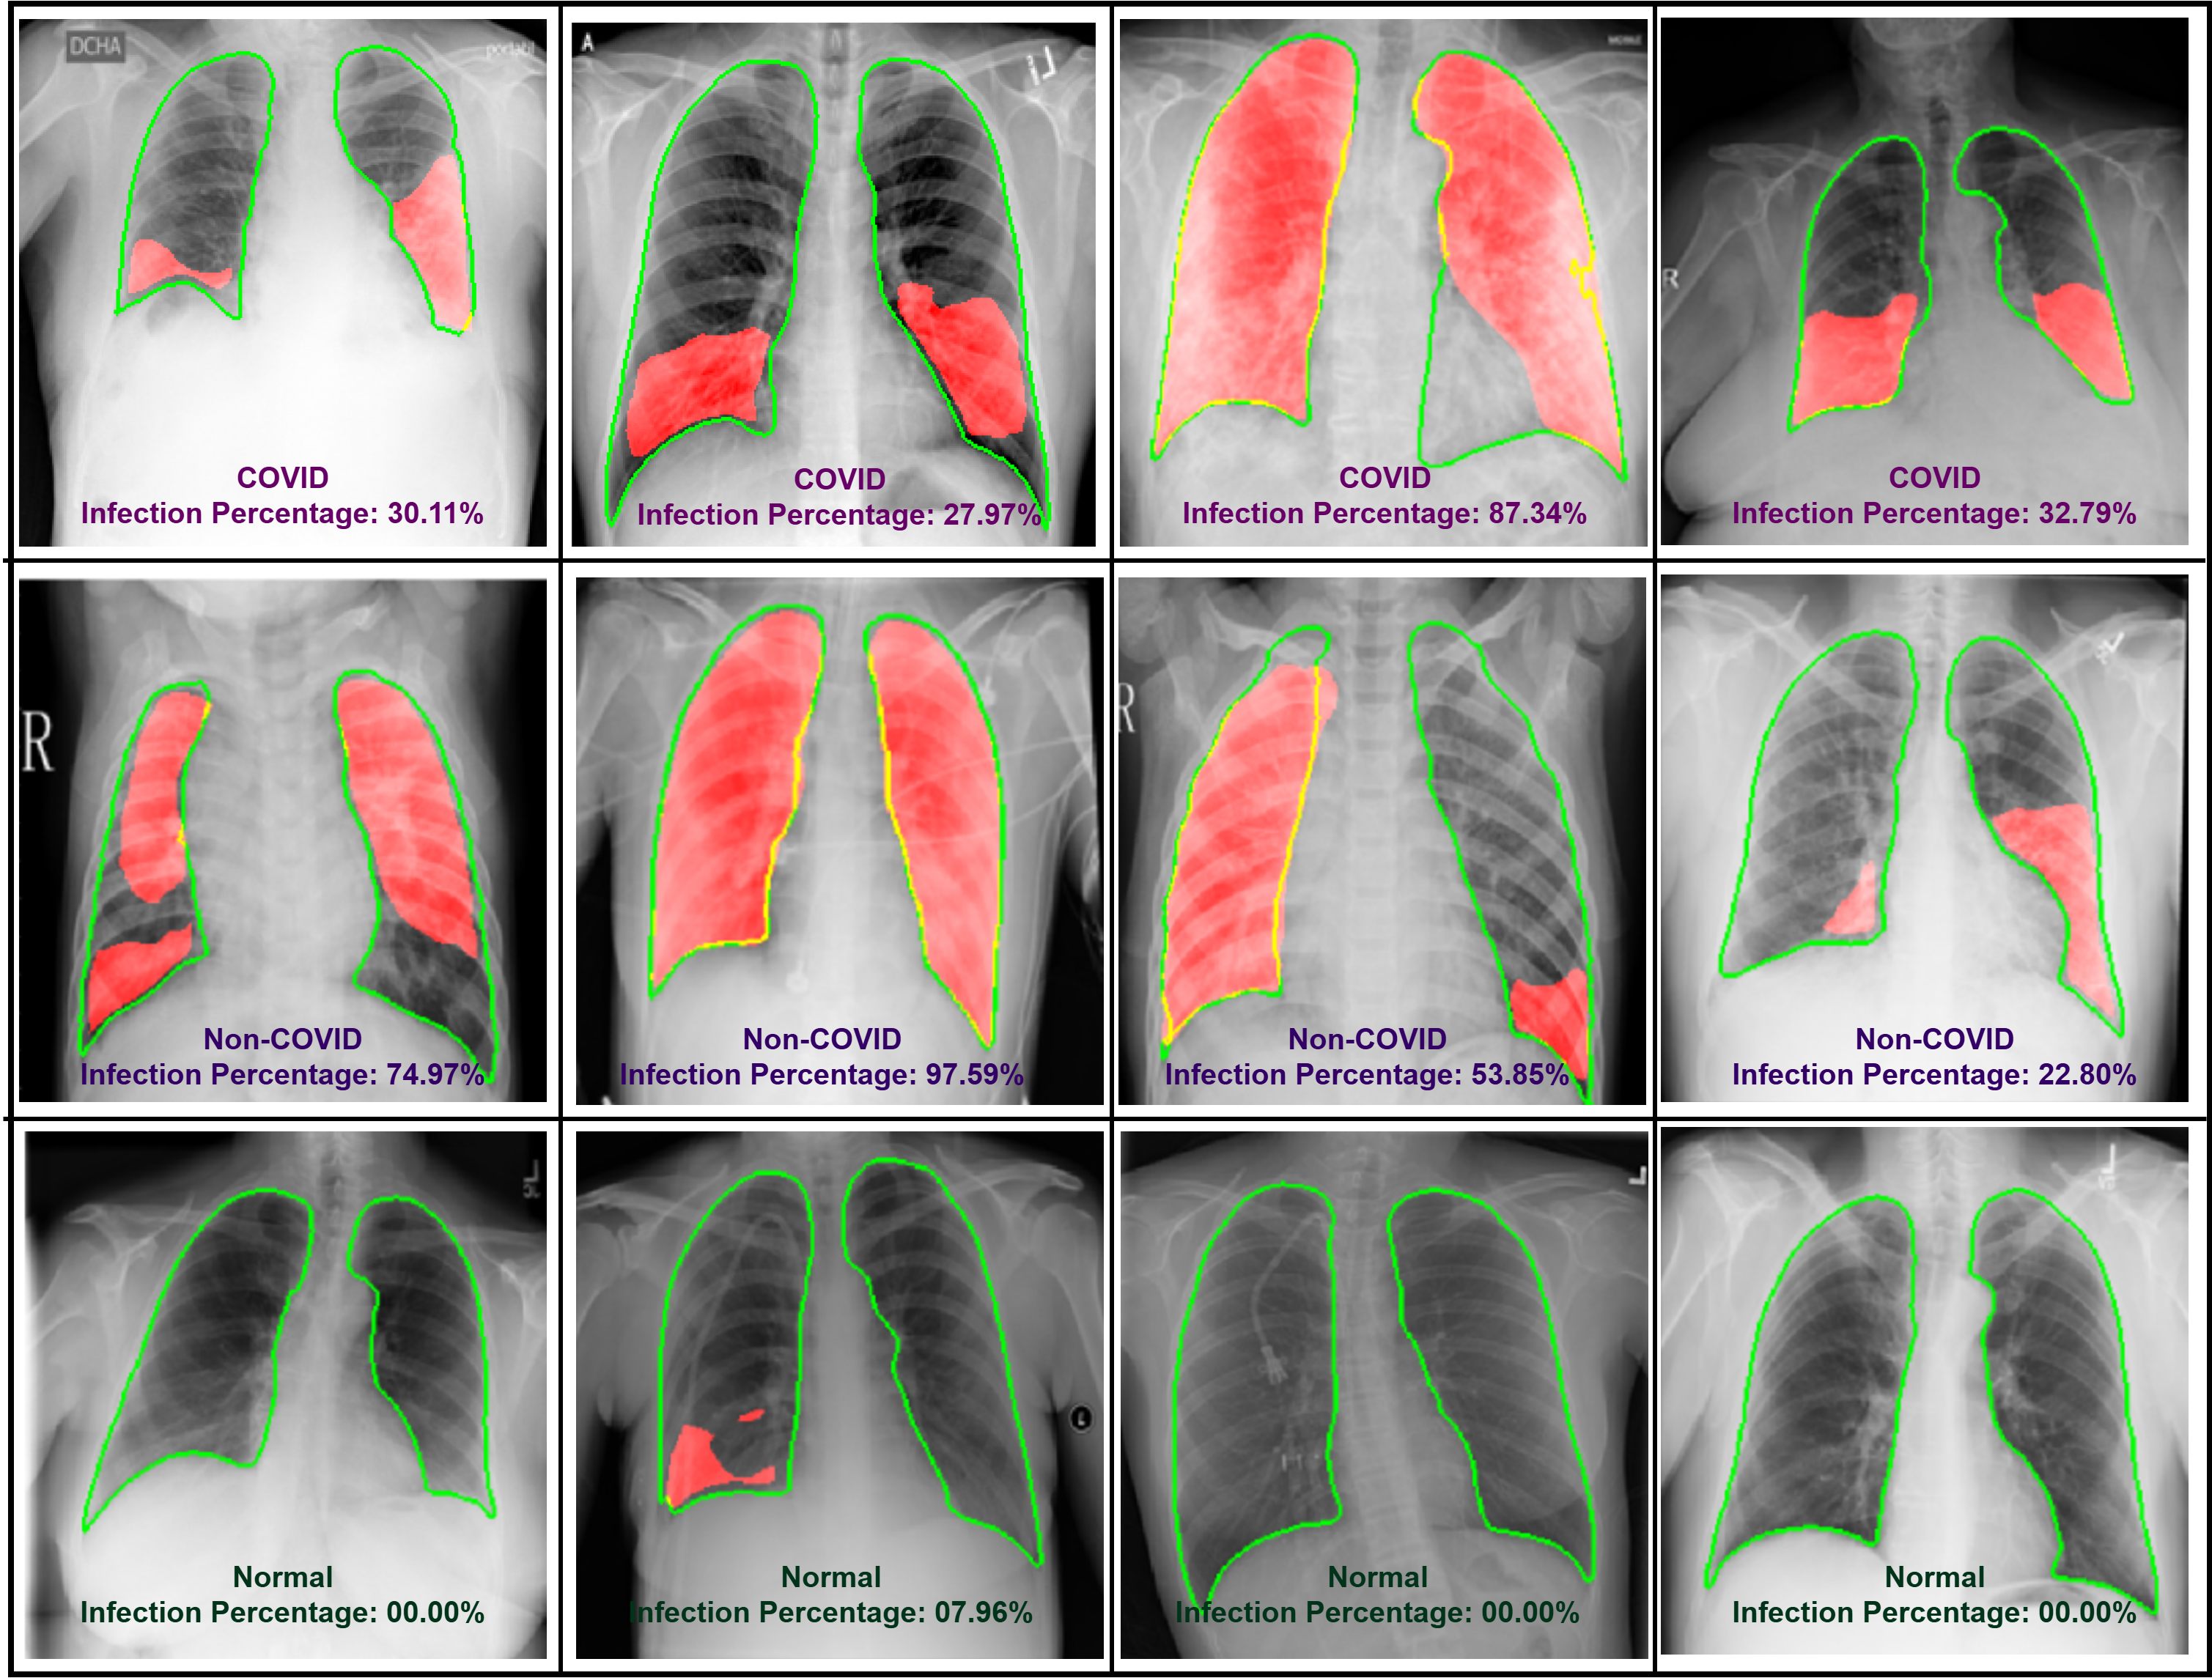

The final operational phase of our lung infection detection system capitalizes on the trained models to analyze chest X-ray images and highlight potential infection regions. This process is pivotal for aiding clinicians in the diagnosis of COVID-19 and non-COVID infections and differentiating these from normal cases.

Figure 13 showcases a series of X-ray images processed through our system. The system accurately delineates lung boundaries for each image and identifies regions showing signs of infection. The infection segmentation model computes the percentage of the affected area, providing quantitative data that supports medical professionals in assessing the severity of the infection.

• COVID and Non-COVID Cases: The images in the first two rows demonstrate cases with significant infection percentages, highlighted in red within the lung contours marked in green. These visualizations differentiate between COVID and non-COVID pneumonia, reflecting the model’s capability to detect, localize, and quantify infection extents.

• Normal Cases: The last row presents normal cases, where the infection percentage is zero or close to zero. These examples are included for reference only to demonstrate the model’s precision in recognizing healthy lung conditions without falsely detecting infections. The system does not generate infection masks for normal cases, ensuring efficient and focused diagnostic processing.

The system’s ability to provide these detailed visual outputs enhances its utility in clinical environments where rapid and accurate assessments are crucial. Such detailed imagery and data facilitate a more informed decision-making process in patient care and treatment strategies.